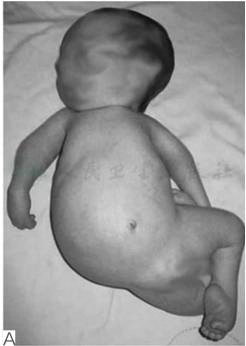

有研究报道,约20%~67%的先天性多发性关节挛缩症患者可出现脊柱侧凸。这类患者往往出生时就表现为脊柱畸形,反映出胎儿在母体宫内位置(图4)。在婴儿期脊柱侧凸进展很快,直至儿童后期才趋于稳定。大多数脊柱侧凸在5岁前可发现,对于肌发育不良及综合征型关节挛缩患者来说,胸弯及胸腰弯更多见,腰弯少见。对远端关节挛缩患者来说,胸腰弯更多见,此类患者侧凸进展比其他类型更快(图5)。

图4肌发育不良新生儿临床特征表现

A.显示明显脊柱侧凸,反应宫内胎位情况;B.同一小孩4岁时行平卧位X线提示腰段30°侧凸;C.同一小孩9岁时行平卧位X线提示腰段42°侧凸(引自Komolkin I, et al. Treatment of Scoliosis Associated With Arthrogryposis Multiplex Congenita.J Pediatr Orthop,2017, 37 Suppl 1:S24-S26.)